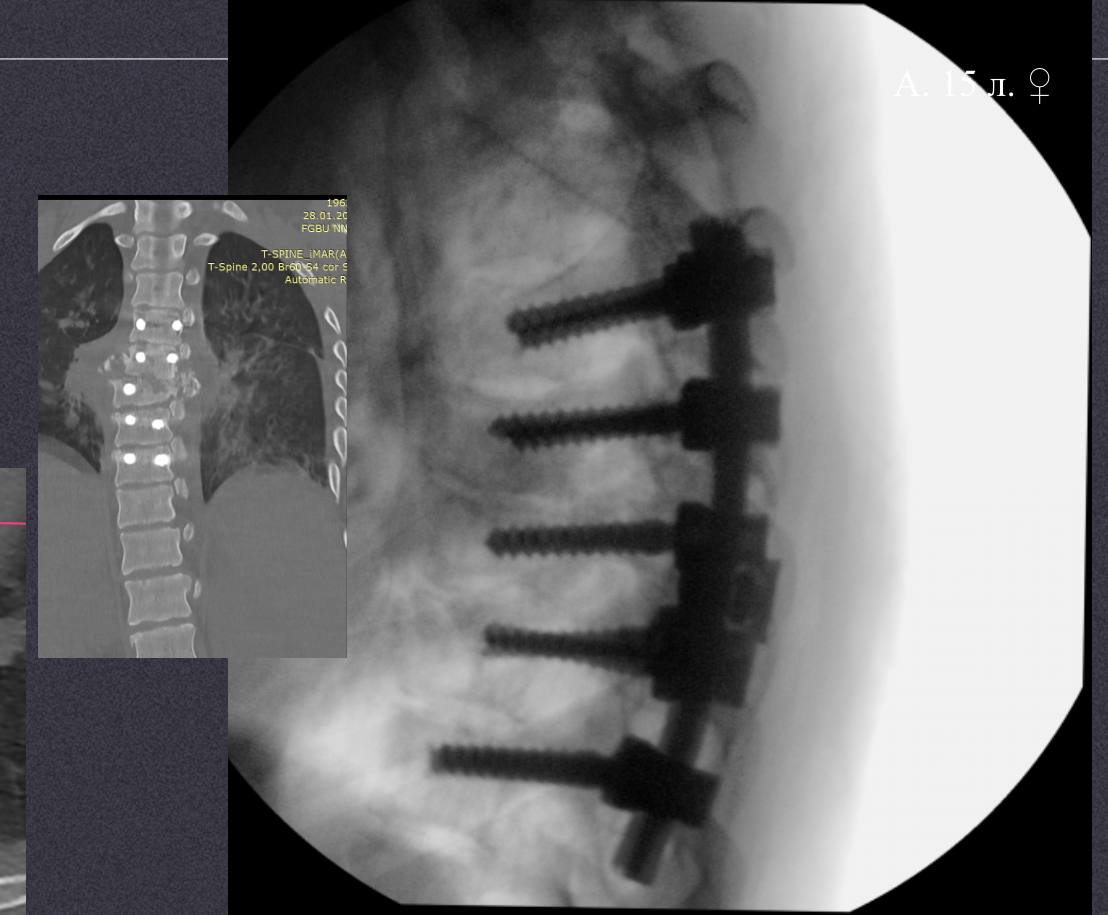

Операция длилась около 9 часов. Спинальные хирурги провели корригирующую вертебротомию — удалили часть поврежденного позвонка, исправили деформацию и зафиксировали позвоночник специальной металлоконструкцией. Во время операции врачи обнаружили, что дуральный мешок цел и пульсирует, что дает надежду на восстановление неврологических функций.